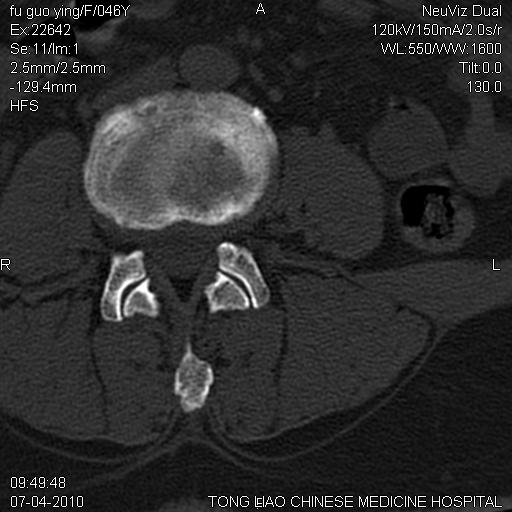

标题: CT27489:患者腰疼,其余椎体未见异常! [打印本页]

标题: CT27489:患者腰疼,其余椎体未见异常!

髂骨考虑转移瘤 椎体病变不像转移瘤

女性46岁,左髂骨溶骨性破坏+软组织肿块,考虑转移瘤,腰椎为退变/增生硬化/软骨下骨囊变。

不排除多发性骨转移瘤可能;建议行进一步检查。